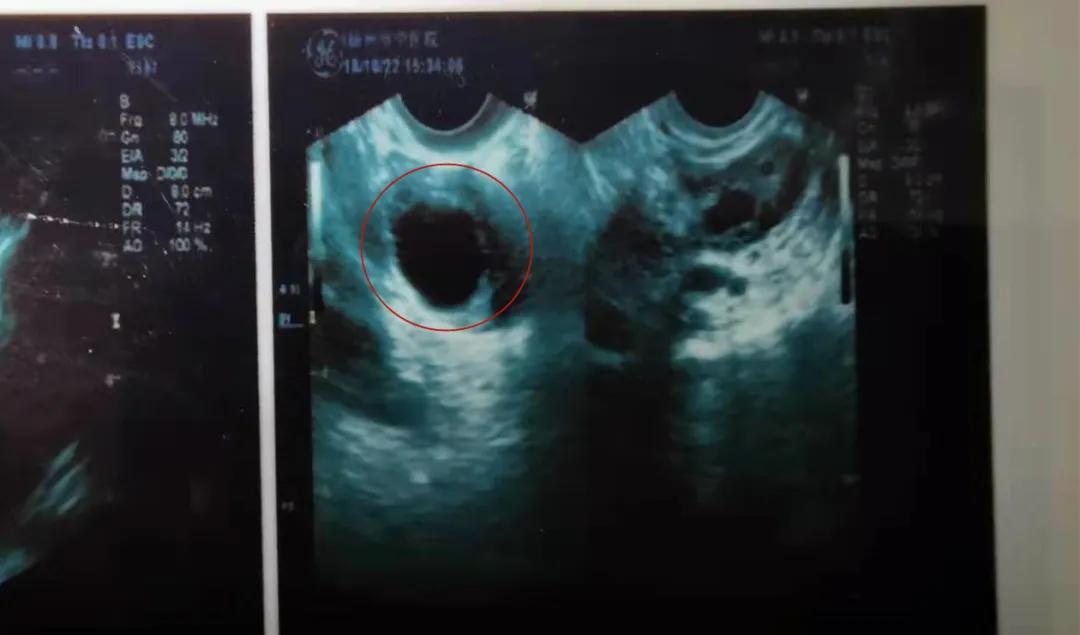

终于,我的B超结果中显示出,我有一个大大大圆圆圆的卵泡了! (感觉那些天,我就像一个焦虑的母鸡,一直在等待自己生蛋……)

B超片上的一颗成熟卵泡,像是潜入未知深海的船~